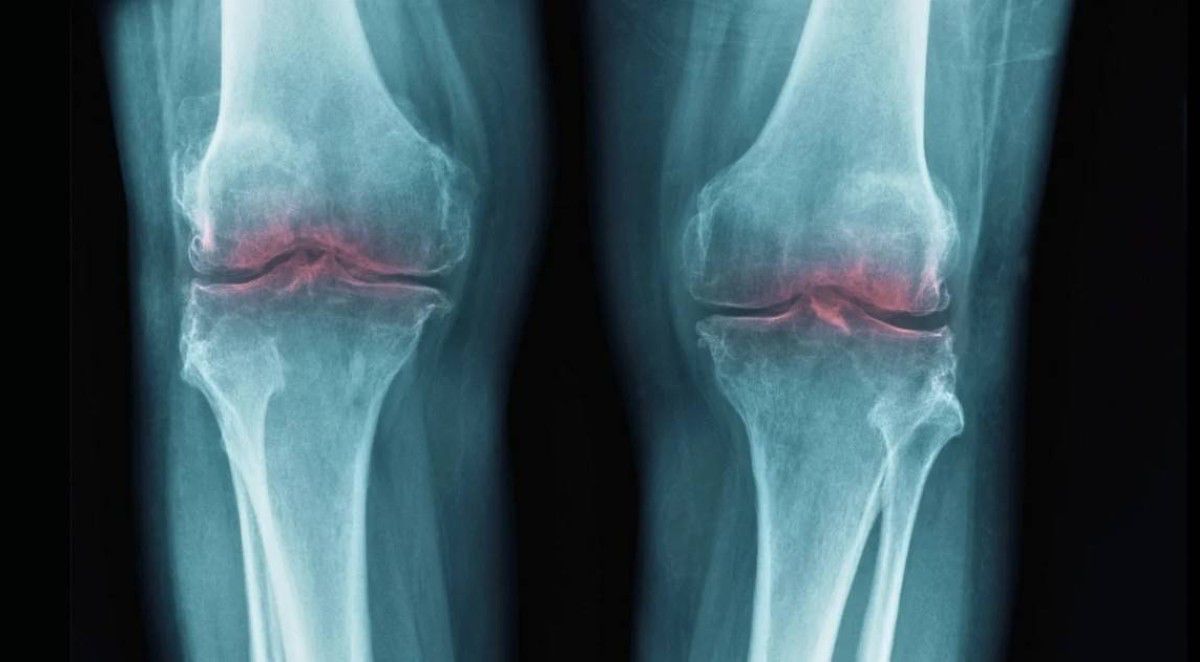

وداعاً للخشونة.. اكتشاف مذهل يجدد الغضروف ويغيّر مستقبل علاج المفاصل

أظهرت دراسة حديثة واعدة أن فقدان الغضروف المرتبط بالشيخوخة قد يكون مرتبطاً ببروتين واحد فقط يُعرف باسم 15-PGDH، مما يفتح الباب أمام إمكانية تطوير علاجات مستقبلية تساعد على ترميم المفاصل المتضررة من التقدم في العمر، وتخفيف أعراض التهاب المفاصل العظمي.

يرتبط هذا البروتين بشكل واسع بعمليات الشيخوخة، إذ يزداد تركيزه مع التقدم في العمر، ويؤثر سلباً على الجزيئات المسؤولة عن إصلاح الأنسجة وتقليل الالتهاب، هذا ما دفع باحثين من جامعة ستانفورد إلى دراسة دوره المحتمل في تدهور المفاصل، خاصة أن التهاب المفاصل يحدث نتيجة تحلل الكولاجين في الغضروف، ما يؤدي إلى الألم والالتهاب وتقييد الحركة.

في تجارب أجريت على فئران مسنة، لاحظ الباحثون أن تثبيط إنزيم 15-PGDH أدى إلى زيادة سماكة غضروف الركبة الذي كان قد تآكل سابقاً وفق sciencealert.

وعند إحداث إصابة مشابهة لتمزق الرباط الصليبي الأمامي لدى الفئران، ثم تطبيق العلاج، لم يتطور المرض كما هو معتاد، ما يشير إلى تأثير وقائي قوي، وقد أظهرت صور الفحص أن الغضروف المعالج في الفئران الأكبر سناً أصبح أقرب في بنيته إلى الغضروف الشاب السليم، من حيث الكثافة والمرونة.

كما تم اختبار الفكرة على عينات بشرية مأخوذة من مرضى خضعوا لجراحة استبدال الركبة، حيث أظهرت النتائج علامات على تحسن في صلابة الغضروف وانخفاض الالتهاب، مما يعزز إمكانية انتقال هذه النتائج إلى التطبيقات البشرية مستقبلاً.